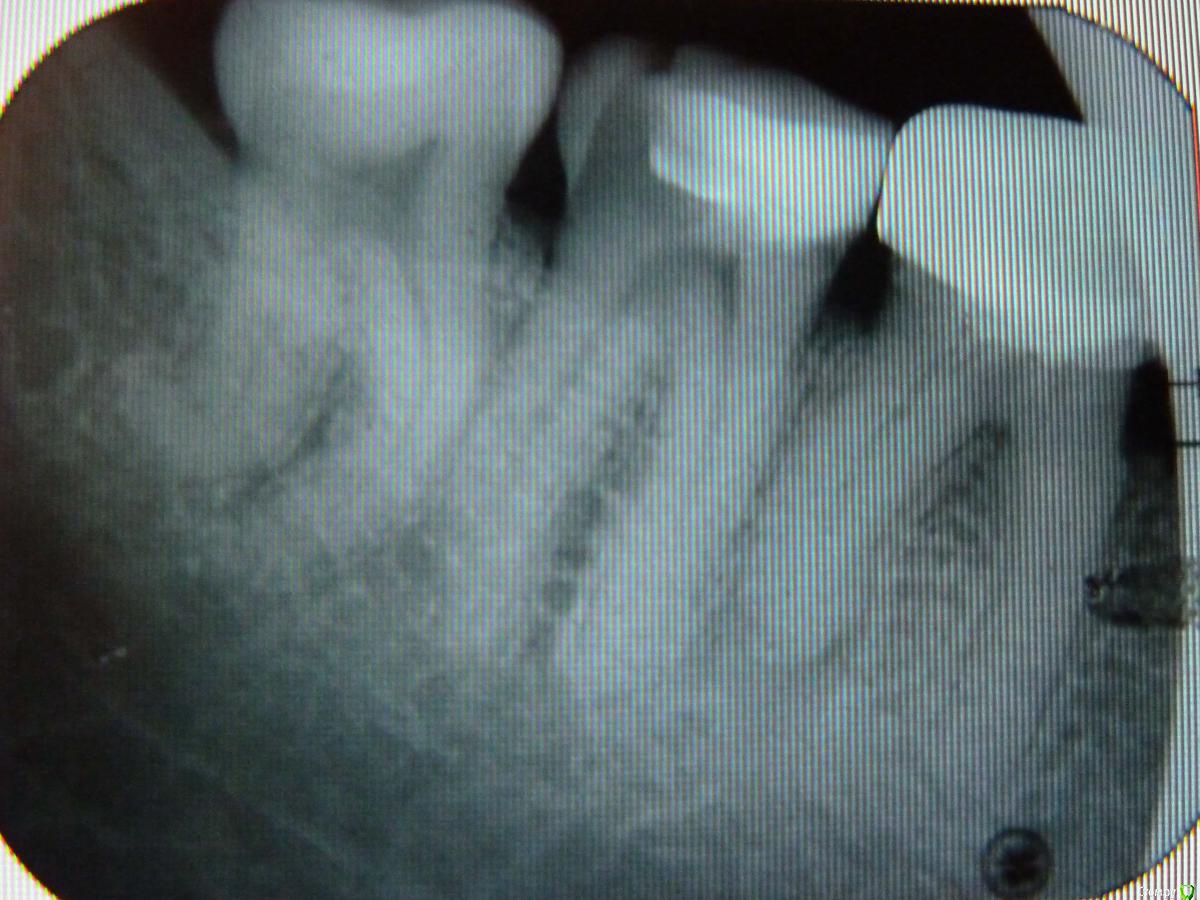

Робинзон Опубликовано 12 декабря, 2014 Поделиться Опубликовано 12 декабря, 2014 От 47-го откололся кусок (часть внутренней стенки), не депульпирован, под большой пломбой. 46-й под коронкой, не беспокоит. Какие посоветуете варианты восстановления? Ссылка на комментарий

red_butler Опубликовано 12 декабря, 2014 Поделиться Опубликовано 12 декабря, 2014 1. Удалить зуб мудрости2. Пролечит седьмой зуб3. снять коронку с шестого зуба и лечить корневые каналы4. протезировать шестой и седьмой зубы 1 Ссылка на комментарий

SDC Опубликовано 12 декабря, 2014 Поделиться Опубликовано 12 декабря, 2014 1. Удалить зуб мудрости2. Пролечит седьмой зуб3. снять коронку с шестого зуба и лечить корневые каналы4. протезировать шестой и седьмой зубы+скороее всего потребуется депульпирование 7-го Ссылка на комментарий

red_butler Опубликовано 13 декабря, 2014 Поделиться Опубликовано 13 декабря, 2014 Спасибо.Подскажите, а 8-ку по какой причине нужно удалять?ухудшает гигиену, и по сути привела к кариесу седьмого зуба. Если пересмотрите отношение к индивидуальной гигиене, и будете вылизывать восьмой зуб как... у кота - то можно и оставить Ссылка на комментарий